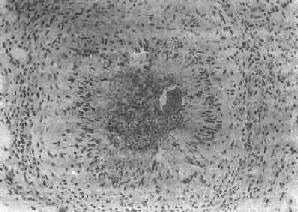

(1)急性虫卵结节:肉眼观为灰黄色、粟粒至绿豆大(0.5~4mm)的小结节。镜下见结节中央常有1~2个成熟虫卵,也偶可多达20个以上。这些成熟虫卵的卵壳上附有放射状嗜酸性的棒状体,也称为Hoeppli现象,用免疫荧光法已证实为抗原抗体复合物。虫卵周围是一片无结构的颗粒状坏死物质及大量嗜酸性粒细胞浸润。因其病变类似脓肿,故也称为嗜酸性脓肿(图19-5)。在坏死组织中可混杂多数菱形或多面形屈光性蛋白质晶体,即Charcot-Leyden结晶,系嗜酸性粒细胞的嗜酸性颗粒互相融合而成。随后虫卵周围产生肉芽组织层,其中有以嗜酸性粒细胞为主的炎症细胞浸润,还有单核巨噬细胞、淋巴细胞、浆细胞及少量中性粒细胞。随着病程的发展,肉芽组织层逐渐向虫卵结节中央生长,并出现围绕结节呈放射状排列的类上皮细胞层。类上皮细胞层逐渐加宽,嗜酸性粒细胞显著减少,构成晚期急性虫卵结节(图19-6),这是向慢性虫卵结节发展的过渡阶段。

肝血吸虫病之急性虫卵结节

图19-5 肝血吸虫病之急性虫卵结节

结节中心有一成熟虫卵,卵壳表面可见放射状物质,周围广泛坏死伴大量嗜酸性粒细胞浸润